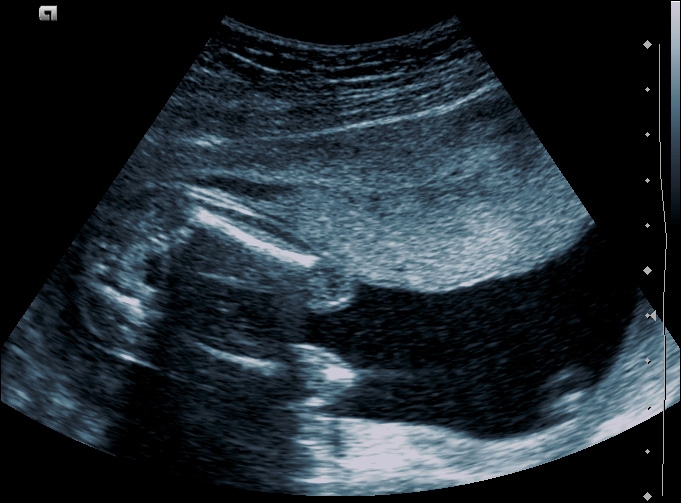

Głównym  celem badania w połowie ciąży jest wykrycie anomalii rozwojowych. Podczas  badania USG bardzo dokładnie zostanie oceniony płód, od czubka głowy, po stopy.

Ma to na celu szczegółową ocenę anatomii, położenia płodu, jego wzrastanie oraz ocena pępowiny, łożyska a także objętości wód płodowych.

Standardowo badanie w 20 tygodniu ciąży wykonywane jest w technice 2D. Jest to aktualnie metoda najdokładniejsza w wykrywaniu ewentualnych anomalii. Dodatkowo można wykonać badanie w technice 3D i 4D, co pozwala na trójwymiarową wizualizację płodu.